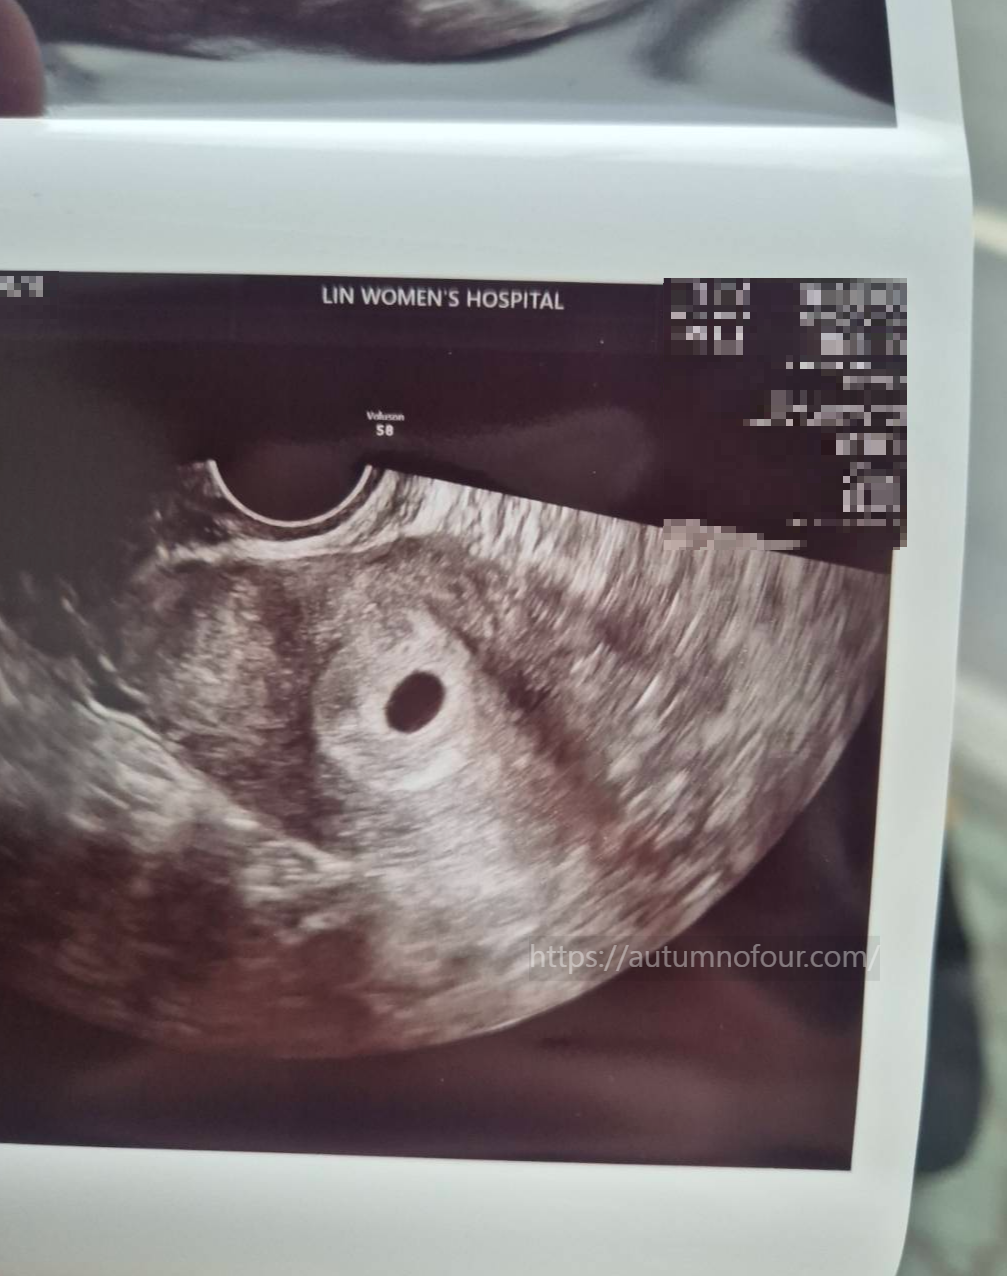

5. 옷을 갈아입고 나오니, 초음파 사진이 뙇!

아기집이 똥~그랗게 뙇!!

10mm의 아주 귀엽고 작은 아기집이 자궁에 아주 잘 자리잡고 있었다.

드뎌 아기집을 보다니.